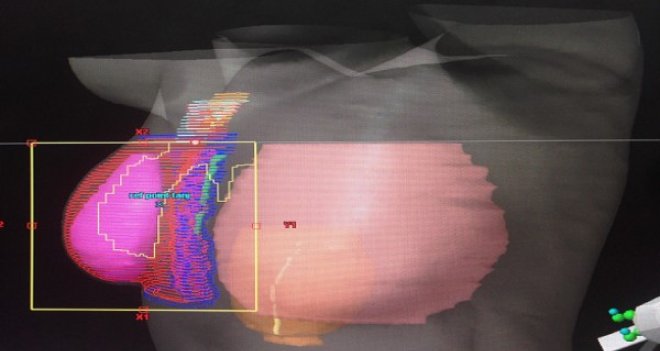

MKC uygulanmış olan ve koltukaltı lenf bezlerinde tümöre bağlı yayılım olmayan hastalarda sadece meme dokusuna, koltuk altında tümör metastazı olan hastalarda ise meme dokusu ile birlikte çevresel lenfatik bölgelere ( koltuk altı) RT uygulanmaktadır. Mastektomi uygulanan hastalarda ise, koltukaltı lenf düğümlerinde tümör metastazı olan, tümör boyutu 5 cm’den büyük, cerrahi sınır pozitifliği olan olgularda sadece göğüs duvarı ve/ veya lenf düğümleri ışınlanmalıdır.      Radyasyon tedavisi planlama işlemi ile başlar, hastanın yatış pozisyonu belirlenir. Hasta bu pozisyonda tomografi cihazına yatırılır ve planlama tomografisi çekilir. Elde edilen tomografi kesitleri, üzerinde her kesitte tedavi edilecek olan bölgeler (meme / göğüs duvarı, lenf düğümleri) ve fazla radyasyondan korunması gereken organlar (kalp, akciğer) belirlenir. Tedavi bölgelerine  maksimum doz verilirken kalp ve akciğer gibi normal dokular en az doza maruz kalacak şekilde radyasyondan korunmaya çalışılır. Özellikle sol meme tedavisinde kalp ve kalbi besleyen sol inen koroner arter dozları çok önemlidir. Bu dozları azaltmak için solunum ayarlı radyoterapi tekniği kullanılmalıdır. Tüm planlama süreci radyasyon onkolojisi uzmanı tarafından yönetilir. Radyasyon tedavisi toplamda 5-6 hafta sürmekte, ışınlama hafta içi beş gün ardışık olarak yapılarak, hafta sonu tedaviye ara verilmektedir. Radyasyon tedavisinden sadece siz ve sizin de doktorunuz tarafından belirlenen bölgeleriniz etkilenir. Tedavi sırasında radyasyon yaymazsınız, aileniz, çocuklarınız ile bir arada bulunabilir, birlikte zaman geçirebilirsiniz.